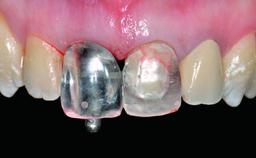

A healthy 23-year-old female patient was referred for a consultation on replacing tooth 21 with an implant-supported restoration. The patient had recently moved to the area and reported a history of endodontic and periodontal treatment for tooth 21. The tooth had been deemed non-restorable by her previous periodontist but since she was going to be moving, he recommended consulting to a dentist in her new city to continue her treatment. A review of her medical history yielded no significant findings and no known drug allergies. The analysis of her smile revealed a medium to high symmetrical smile line and a slightly discolored tooth 21.